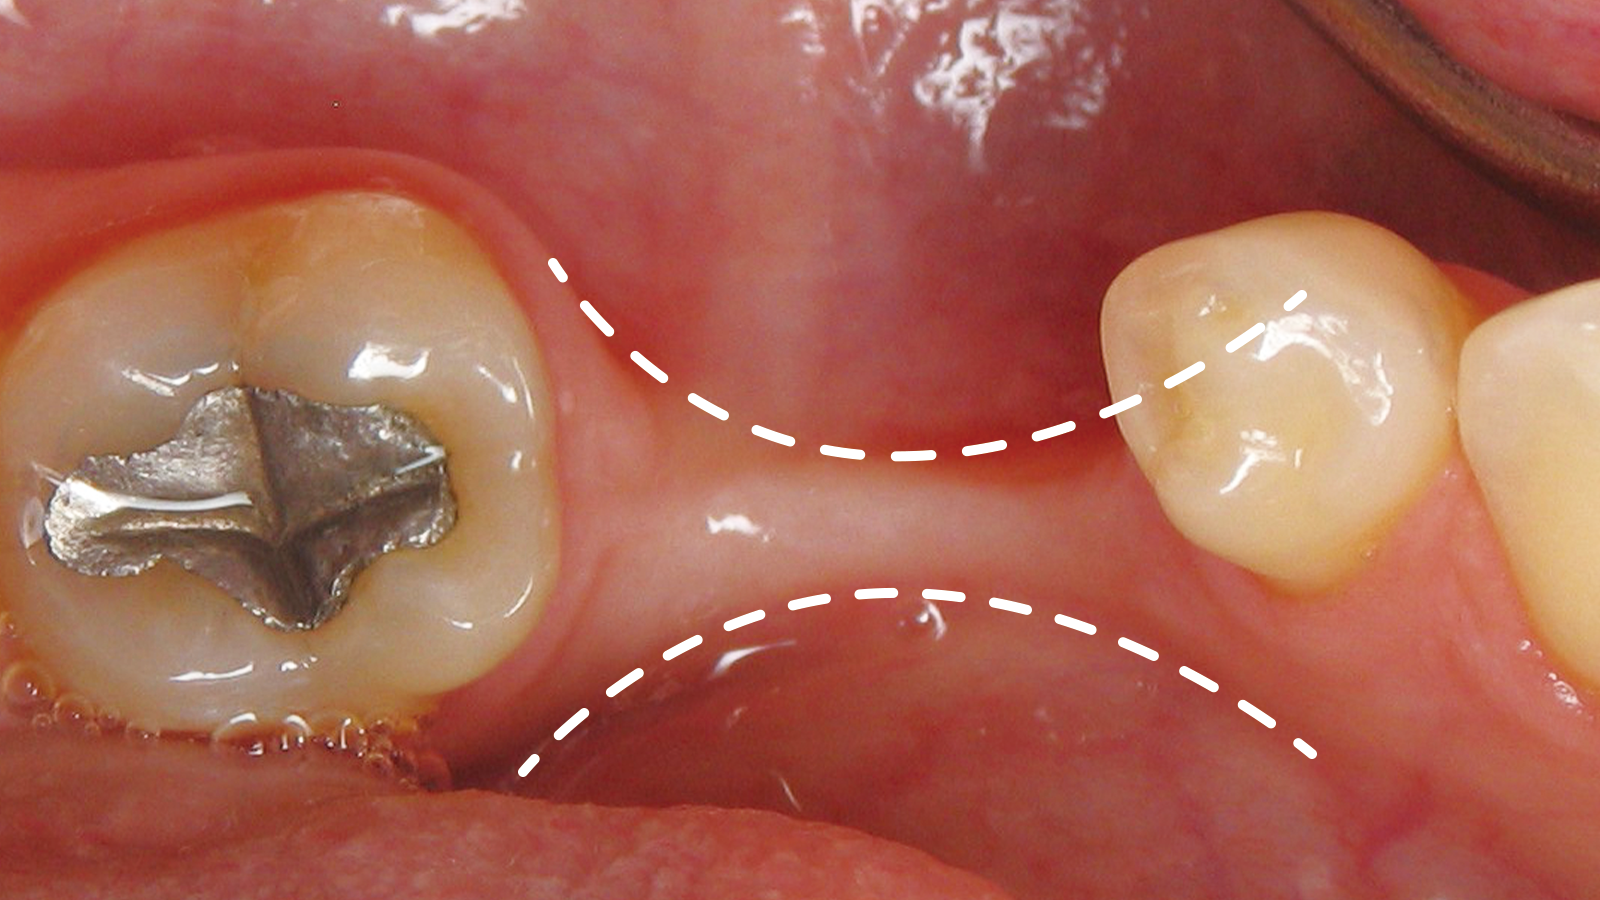

발치 후 시간 경과에 따른 잇몸뼈의 두께 변화

뼈이식 양이 많은 경우

뼈이식술 3-6개월 후 임플란트 식립

뼈이식 양이 적은 경우

뼈이식과 동시에 임플란트 식립

잇몸뼈가 부족해도

임플란트 할 수 있나요?

잇몸의 폭이 좁으면 안정적인 임플란트 식립이 어려워

잇몸뼈를 쪼갠 후 공간을 넓히는 수술을 합니다.

잇몸뼈가 부족해도 임플란트 할 수 있나요?

잇몸의 폭이 좁아지면 안정적인 임플란트 식립이 어려우므로

잇몸뼈를 쪼갠 후 공간을 넓히는 릿지 스플릿 수술을 진행하게 됩니다.

릿지 스플릿 진행 단계